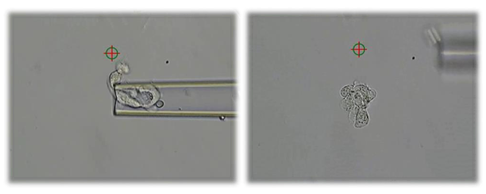

Selve biopsi-tagningen foregår ved at skyde et lille hul i embryonets skal. Herigennem suger vi trophectodermceller ud og op i en tynd pipette. Med laseren kan vi adskille de udtagne celler fra resten af de tilbageblevne trophectodermceller.

Med laser skydes der et hul i æggets skal og ved hjælp af pipetten suges celler ud Disse adskilles fra de resterende trophectodermceller ved hjælp af laseren.

Her ses en biopsi, der består af cirka 7 celler i pipetten. Når cellerne er adskilt fra blastocysten, bliver de overført til en anden bakke, hvor de vaskes, lynfryses og sendes til analyse.